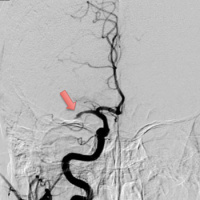

• Endovascular Thrombectomy and Outcomes in Ischemic Stroke

27/09/2016 Duración: 03min

Interview with Jeffrey L Saver, M.D., author of Time to Treatment With Endovascular Thrombectomy and Outcomes From Ischemic Stroke: A Meta-analysis